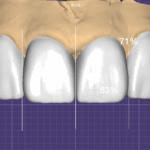

세라믹 제작: 두께의 한계 극복

다층 빌드업의 전략적 적용

이 케이스의 가장 큰 도전은 두꺼운 라미네이트를 자연스럽게 만드는 것이었습니다.

색상 설계 전략:

내부 코어층:

- 노출된 상아질 색상 차폐

- 중간 명도의 기본 색조

- 40대 여성에 적합한 따뜻한 톤 포함

중간 전이층:

- 복수의 세라믹 분말 전략적 혼합

- 치경부에서 절단연으로의 자연스러운 명도 변화

- 내부 특성화(internal characterization)로 깊이감 부여

외부 법랑질층:

- 적절한 투명도 부여

- 절단연 투명 영역 재현

- 자연 치아의 광학적 특성 모방

표면 마무리:

- 미세 질감(texture) 부여

- 발육엽과 횡문 재현

- 적절한 광택도 조절

핵심 원칙: 두께가 있더라도 다층 구조와 적절한 광학 설계로 자연스러움을 구현할 수 있습니다. 이는 단일 블록 재료로는 불가능하며, 숙련된 기공사의 손작업이 필수입니다.